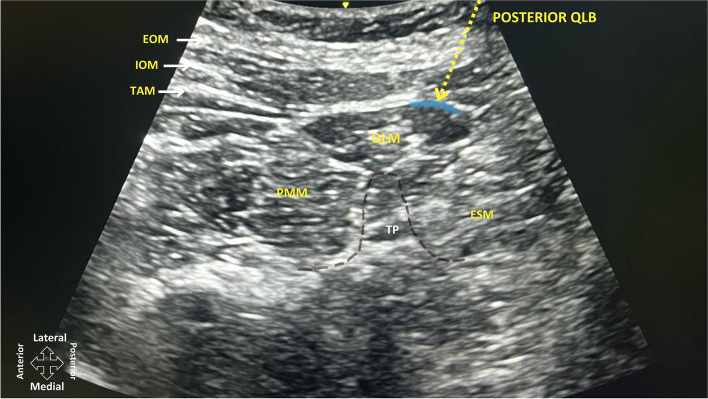

Background: Effective postoperative pain management is crucial in caesarean delivery (CD) to enhance recovery, minimize opioid use, and improve maternal outcomes. Intrathecal morphine (ITM) is widely used but can cause side effects, such as pruritus and nausea. Posterior quadratus lumborum block (QLB) has emerged as a potential alternative for postoperative analgesia. This study compared the analgesic efficacy and side-effect profiles of ITM and posterior QLB in patients with CD.

Methods: This prospective observational study included parturients who underwent elective CD under spinal anesthesia. Participants were allocated to receive either ITM (100 µg) or bilateral posterior QLB with 0.25% bupivacaine (25 mL per side). The primary outcome was cumulative intravenous morphine consumption 24 h post-surgery. The secondary outcomes included NRS pain scores at rest and during activity at 0, 3, 6, 12, and 24 h, the time to first opioid request, the number of patients requiring rescue analgesia, nausea and vomiting scores, pruritus scores, and scores on the Obstetric Quality of Recovery Scale (ObsQoR-11 T) at 24 h and 48 h postoperatively.